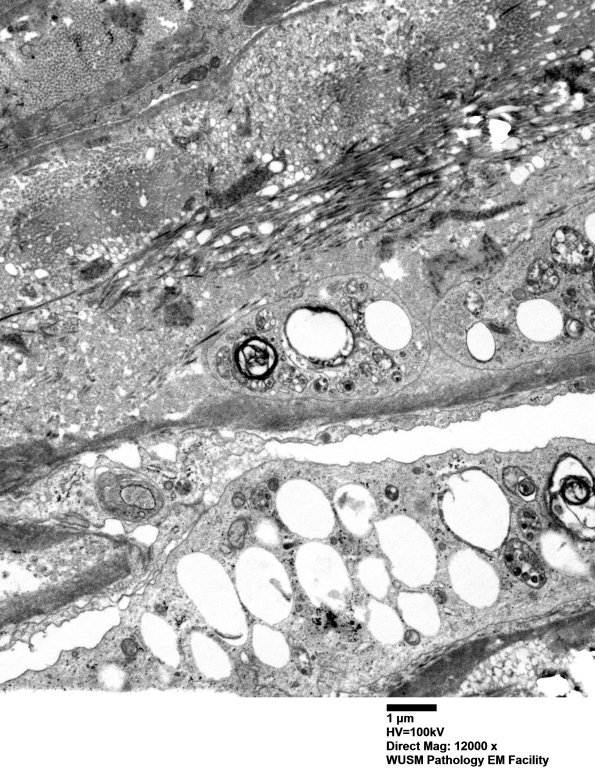

2D1,2 Ultrastructure of the perineurium shows numerous lipid laden macrophages. (electron micrographs)